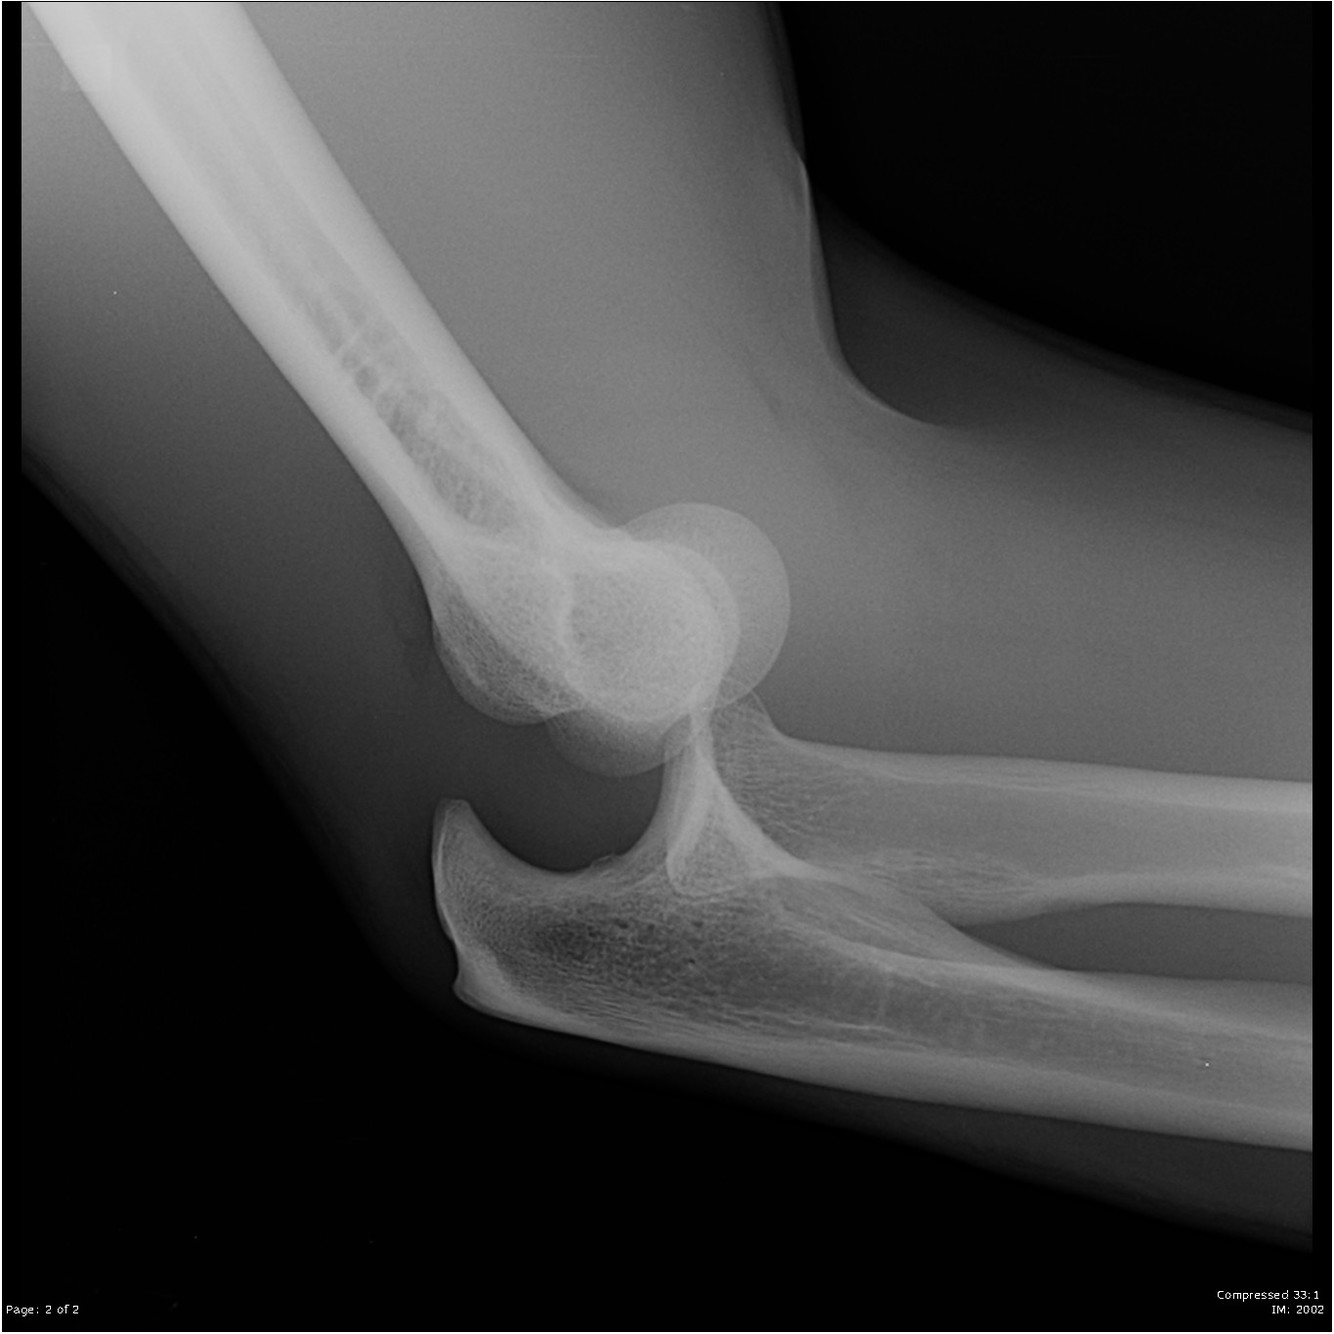

What is an elbow dislocation?

What is a supracondylar fracture of the distal humerus?

What are radial head/neck fractures?